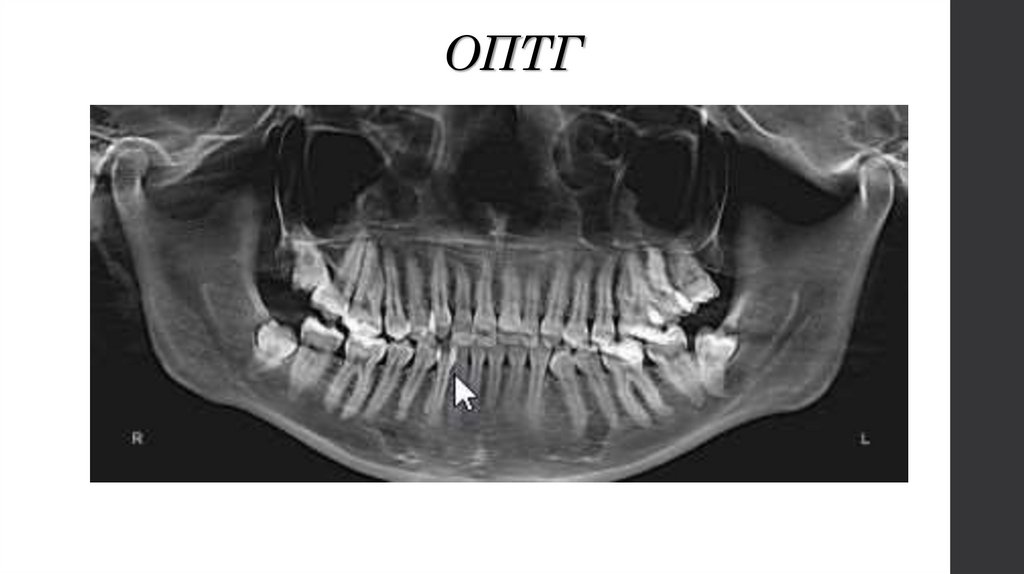

ОПТГ

11. ОПТГ